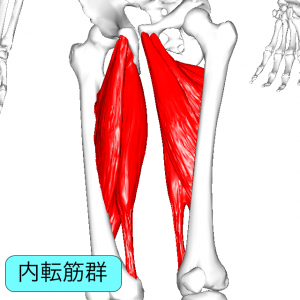

太ももの内側には、大内転筋、長内転筋などの股関節内転筋群という筋肉群があります。内転筋は股関節を内転させる、股を閉じる動きに関わる筋肉で、3層の筋肉層によって構成されています。

第1層(表層)は恥骨筋・薄筋・長内転筋の3つの筋肉があります。第2層(中間層)には短内転筋があります。第3層(深層)には大内転筋・小内転筋があります。これら3つの筋肉を内転筋群と言います。内転筋群に痛みを感じた場合、炎症を起こしている状態は内転筋群炎症になります。

炎症を起こしてしまう原因は色々あります。変形性股関節症、関節リウマチなど病気からくる場合、O脚やX脚など骨格の歪みからくるものになります。腰や足首、足の裏などの痛みをかばうことによっても炎症を起こしてしまうことがあります。症状としては太ももの内側の痛みになりますが、炎症を起こしている筋肉によって痛む場所が変わってきます。太ももの付け根あたりから膝の上あたりまで、筋肉の伸びる部位のどこかで痛みを感じます。